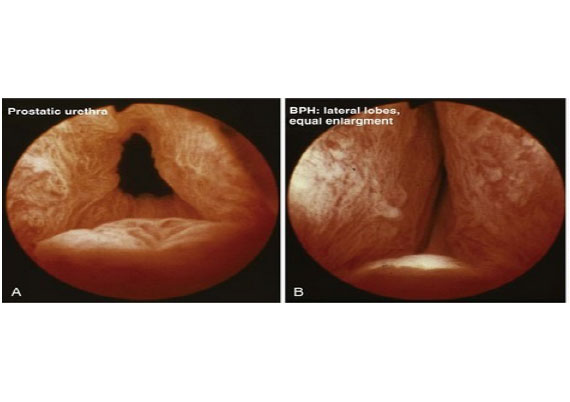

The prostate is a gland that sits at the exit of the bladder. In a young man it is 15-25 cc in volume. Imagine it as a ring donut, with urine passing through the donut hole in the centre. As one grows older, the donut often enlarges, and the hole at the centre closes off, obstructing the flow of urine. This happens most commonly due to a benign process where abnormal tissue growth expands from the centre part of the prostate, replacing the normal central tissue, and compressing the normal glandular tissue at the edge of the prostate gland. This is termed BPH- Benign Prostate Hyperplasia.

HoLEP aims to remove all the abnormal BPH tissue, which is not possible with TURP in a large gland, over 80cc. A laser fibre is used to access a plane between the prostate capsule and the abnormal BPH adenoma, and the adenoma is then ‘shelled out’ and dropped into the bladder. It is then broken down and removed using a special tool. The tissue removed is then sent to the lab for histological analysis. A urinary catheter is placed and the bladder is washed out until the next morning. The catheter is then removed and you are sent home to recover.